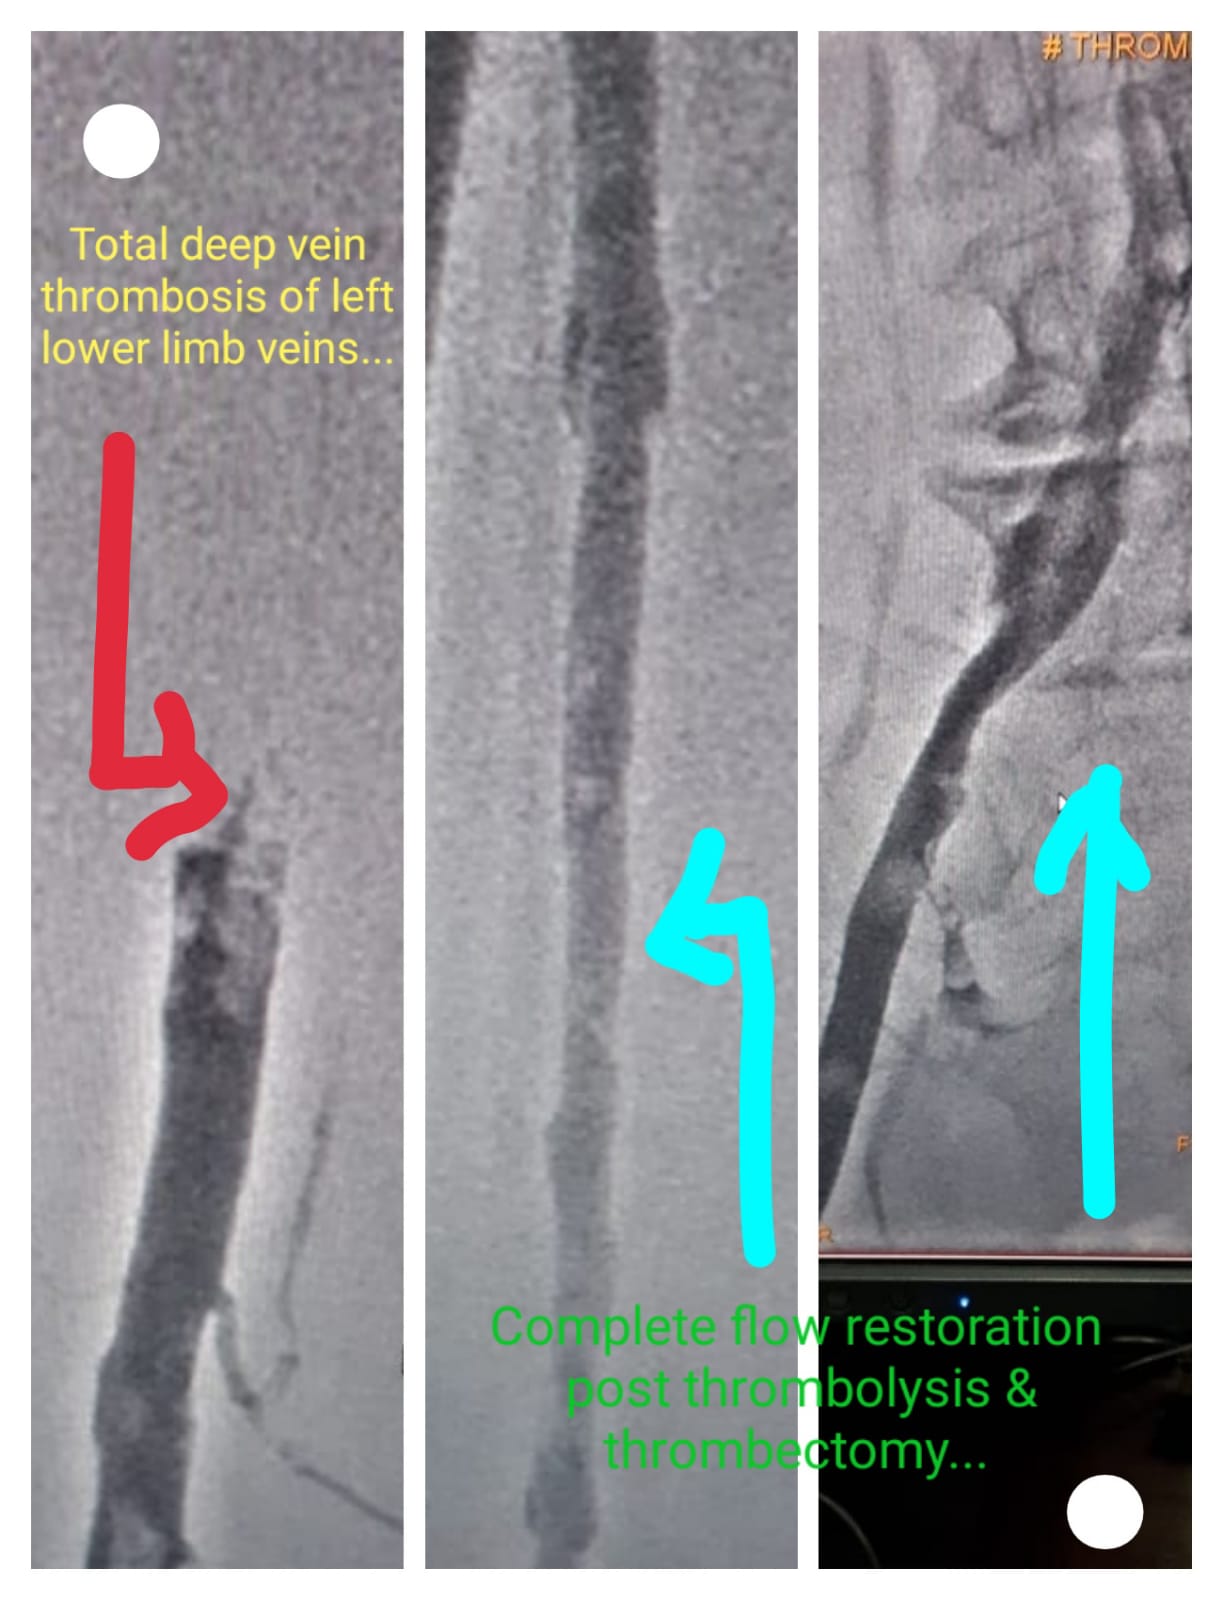

Deep Vein Thrombosis (DVT) in left leg. Pre Procedure - No Flow & Post Procedure- Complete flow restoration post thrombolysis & Thrombectomy.